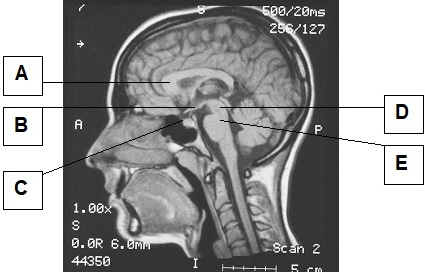

Która z zaznaczonych struktur wewnątrzczaszkowych widocznych na obrazie rezonansu magnetycznego należy pod podwzgórza?